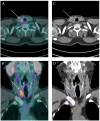

Due to its overexpression on the surface of prostate cancer cells, prostate-specific membrane antigen (PSMA) is a relatively novel effective target for molecular imaging and radioligand therapy (RLT) in prostate cancer. Recent studies reported that PSMA is expressed in the neovasculature of various types of cancer and regulates tumour cell invasion as well as tumour angiogenesis. Several authors explored the role of diagnostic and therapeutic PSMA radioligands in various malignancies. In this narrative review, we describe the current status of the literature on PSMA radioligands' application in solid tumours other than prostate cancer to explore their potential role as diagnostic or therapeutic agents, with particular regard to the relevance of PSMA radioligand uptake as neoangiogenetic biomarker. Hence, a comprehensive review of the literature was performed to find relevant articles on the applications of PSMA radioligands in non-prostate solid tumours. Data on the general, methodological and clinical aspects of all included studies were collected. Forty full-text papers were selected for final review, 8 of which explored PSMA radioligand PET/CT performances in gliomas, 3 in salivary gland malignancies, 6 in thyroid cancer, 2 in breast cancer, 16 in renal cell carcinoma and 5 in hepatocellular carcinoma. In the included studies, PSMA radioligand PET showed promising performance in patients with non-prostate solid tumours. Further studies are needed to better define its potential role in oncological patients management, especially in those undergoing antineoangiogenic therapies, and to assess the efficacy of PSMA-RLT in this clinical context.